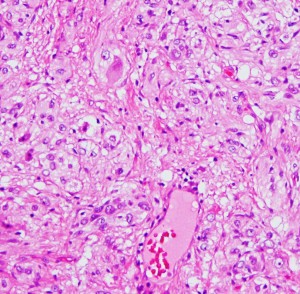

大小の神経細胞とグリア細胞が混在して存在します

小型のグリア細胞にも多少の異型があり腫瘍性グリアと考えられます

グレード1のgangliogliomaです

大脳皮質に大型の核を有する円形の神経細胞が散在しています。神経細胞間にグリア細胞がありますが腫瘍性増殖を示しません。MIB-1は1%以下でした。血管周囲にリンパ球浸潤があります。

構成要素はGFAP陽性の膠細胞が多く認められます。神経細胞様形態の細胞 ganglion cellではNeuN(+), CGA (+) synaptophisin (++), neurofilament (+)です。大型で腫大した核を有して核内封入体構造を有する好酸性もしくは淡明な細胞質を有する細胞が増殖してPXAを考えさせる部分像もありました。granular bodyも認められて,右の写真のように膠原線維の増生が目立つ部分もあります。これは表面の非常に硬い線維性の腫瘍部分です。MIB-1 indexは4%とやや高い値です。BRAF v600Eの変異が認められました。